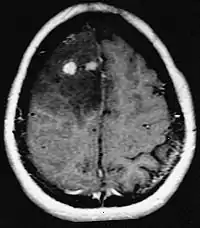

Hjernemetastaser er de mest almindelige intrakranielle neoplasmer hos voksne og er ti gange hyppigere end primære hjernetumorer. De træder til 20 indtil 40 procent af voksne med kræft og er hovedsageligt forbundet med lunge- og brystkræft og melanom . Disse læsioner skyldes spredning af kræftceller gennem blodbanen og forekommer oftest ved krydset mellem gråt og hvidt stof, hvor tværsnittet af blodkar ændres, hvilket fanger tumorcelleemboli . 80 procent af læsionerne forekommer i cerebrale hemisfærer, 15 procent i lillehjernen og 5 procent i hjernestammen. Omkring 80 procent af patienterne har en historie med systemisk cancer og 70 procent har flere hjernemetastaser.

Der er for nylig gjort betydelige fremskridt i diagnosticering og behandling af disse læsioner, hvilket resulterer i forbedret overlevelse og symptomkontrol. Begyndelsen af tegn og symptomer ligner dem ved andre massive læsioner i hjernen. Den valgte diagnostiske metode er magnetisk resonansbilleddannelse ved hjælp af kontrastmidler.

Litteraturen viser tilsvarende resultater for kirurgi og strålekirurgi. Sidstnævnte ser ud til at være mere bekvem, effektiv og mere sikker for små læsioner eller i områder, der er utilgængelige for kirurgi. Strålekirurgi er et fornuftigt alternativ til patienter, der af medicinske årsager ikke kan opereres. Kirurgi er dog klart den optimale metode til at opnå væv til diagnosticering og til at fjerne de læsioner, der forårsager masseeffekt. Derfor bør strålekirurgi og kirurgi bedre betragtes som to komplementære, men forskellige metoder, der skal anvendes afhængigt af patientens forskellige situation. For næsten 50 procent af patienter med en eller to hjernemetastaser er ikke kandidater til kirurgisk fjernelse på grund af utilgængelighed af læsionerne, omfanget af systemisk sygdom eller andre faktorer. Disse og andre patienter med flere metastaser tilbydes normalt panencefalisk strålebehandling som standardbehandling. Faktisk nå op til næsten 50 procent af dem med denne terapi en forbedring af neurologiske symptomer og 50 indtil 70 procent en mærkbar reaktion.[6][7][8] Kemoterapi bruges sjældent primært til hjernemetastaser.